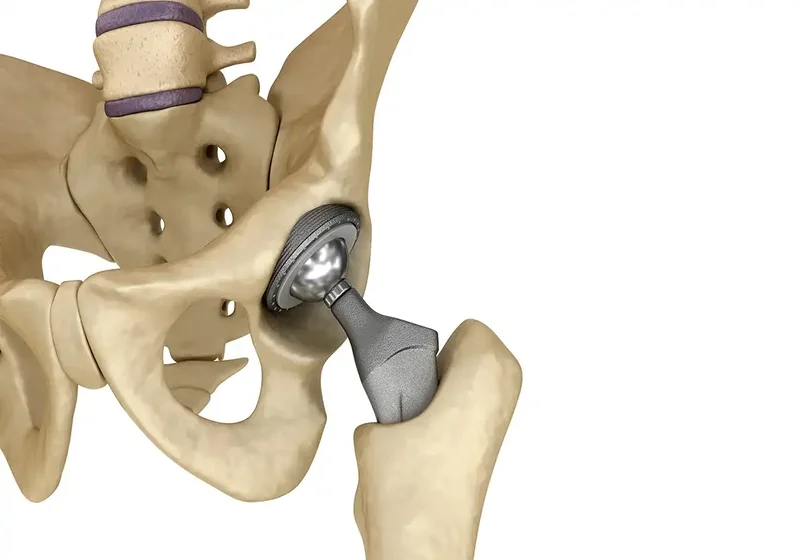

A cirurgia minimamente invasiva oferece uma alternativa promissora para o tratamento de condições no joelho e quadril, com benefícios significativos para os pacientes.

1. Menor trauma cirúrgico:

As técnicas minimamente invasivas geralmente utilizam incisões menores, o que resulta em menos trauma para os tecidos circundantes. Isso pode ajudar a reduzir a dor pós-operatória e acelerar a recuperação.

2. Recuperação mais rápida:

Pacientes que se submetem a cirurgias minimamente invasivas tendem a ter um tempo de recuperação mais curto. A diminuição do trauma cirúrgico facilita o retorno às atividades diárias e esportivas.

3. Menor risco de complicações:

Com menos invasão nos tecidos, há uma redução no risco de complicações como infecções e hemorragias. Isso resulta em um período de internação hospitalar mais curto e uma recuperação mais segura.

4. Menores cicatrizes:

As incisões menores resultam em cicatrizes menos visíveis, o que pode ser um fator importante para muitos pacientes que se preocupam com a estética após a cirurgia.

5. Menos dor pós-operatória:

Graças ao menor trauma e à abordagem menos invasiva, muitos pacientes relatam menos dor após a cirurgia, permitindo um controle mais fácil da dor com medicamentos simples.